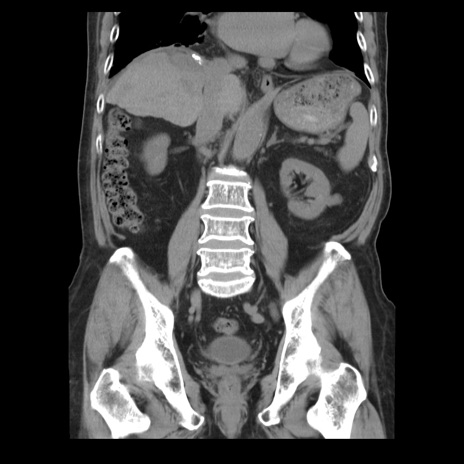

横断像

【症例】70歳代男性

【主訴】腹痛

【現病歴】肝硬変・肝細胞癌にてかかりつけの方。約9時間前に食後より腹痛出現。症状が徐々に増悪し、嘔吐出現したため来院。

【既往歴】肝硬変、肝細胞癌(RFA、TACE後)

【身体所見】意識清明、表情苦悶様、BT 36℃、BP 129/78mmHg、P 88bpm、SpO2 97%(RA)、右上腹部から心窩部にかけて圧痛あり、反跳痛なし、筋性防御あり。

【データ】WBC 5800、CRP 0.16